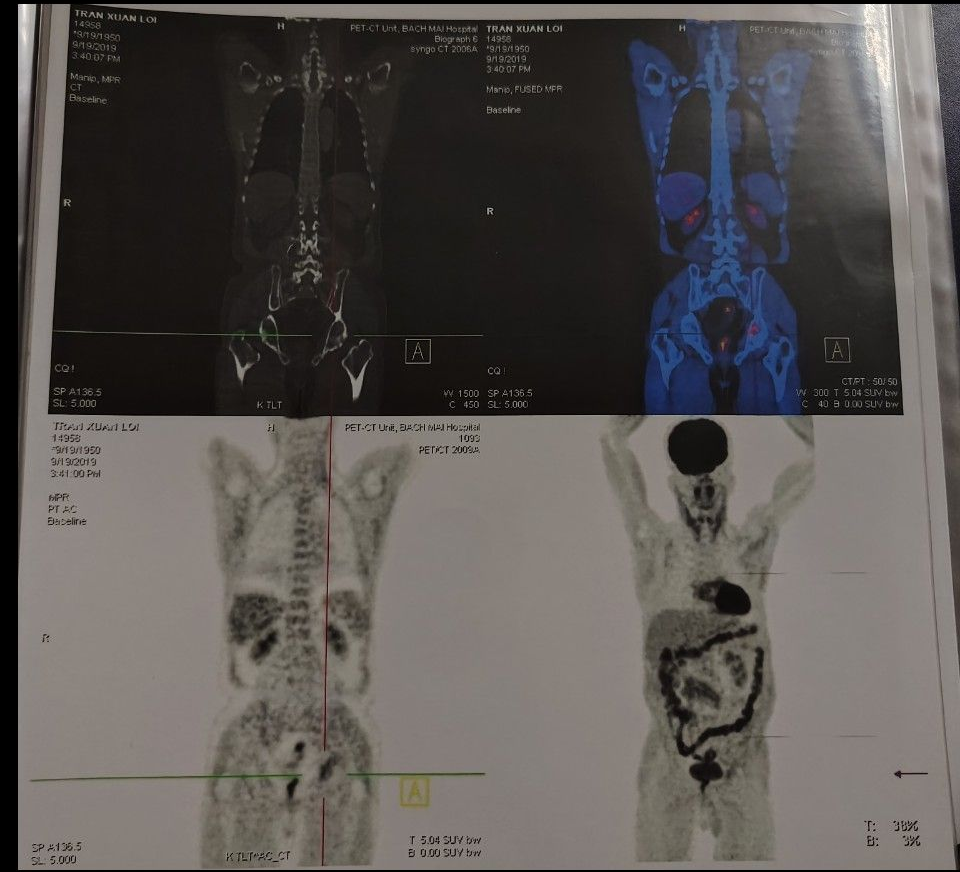

- Chụp PET-CT toàn thân với F-18 FDG (cách vào viện 4 năm):

+ Tổn thương xương chậu trái tăng hấp thu F-18FDG, max SUV = 3,78

+ Không thấy tổ chức tăng hấp thu F-18 FDG bất thường tại các vị trí khác trong cơ thể

Kết luận: Hình ảnh tổn thương xương chậu trái tăng hấp thu FDG (dạng tổn thương thứ phát).

Hình ảnh PET-CT toàn thân với F-18FDG: Tổn thương xương chậu trái tăng hấp thu F-18FDG